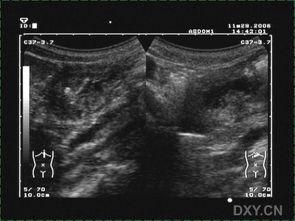

超声胃视频,顾名思义,就是利用超声波来观察胃部的一种检查方法。它的工作原理是这样的:医生会先让你喝下一杯含有微泡的液体,这些微泡会随着胃的蠕动而移动,从而产生回声。医生将超声探头放在你的腹部,通过调整探头与胃部的距离和角度,就可以清晰地观察到胃壁、胃腔、胃窦等部位的情况。

超声胃视频在临床上的应用非常广泛。它可以用于诊断胃炎、胃溃疡、胃息肉、胃癌等胃部疾病。此外,对于胃部手术后的患者,超声胃视频还可以用于观察胃部恢复情况。